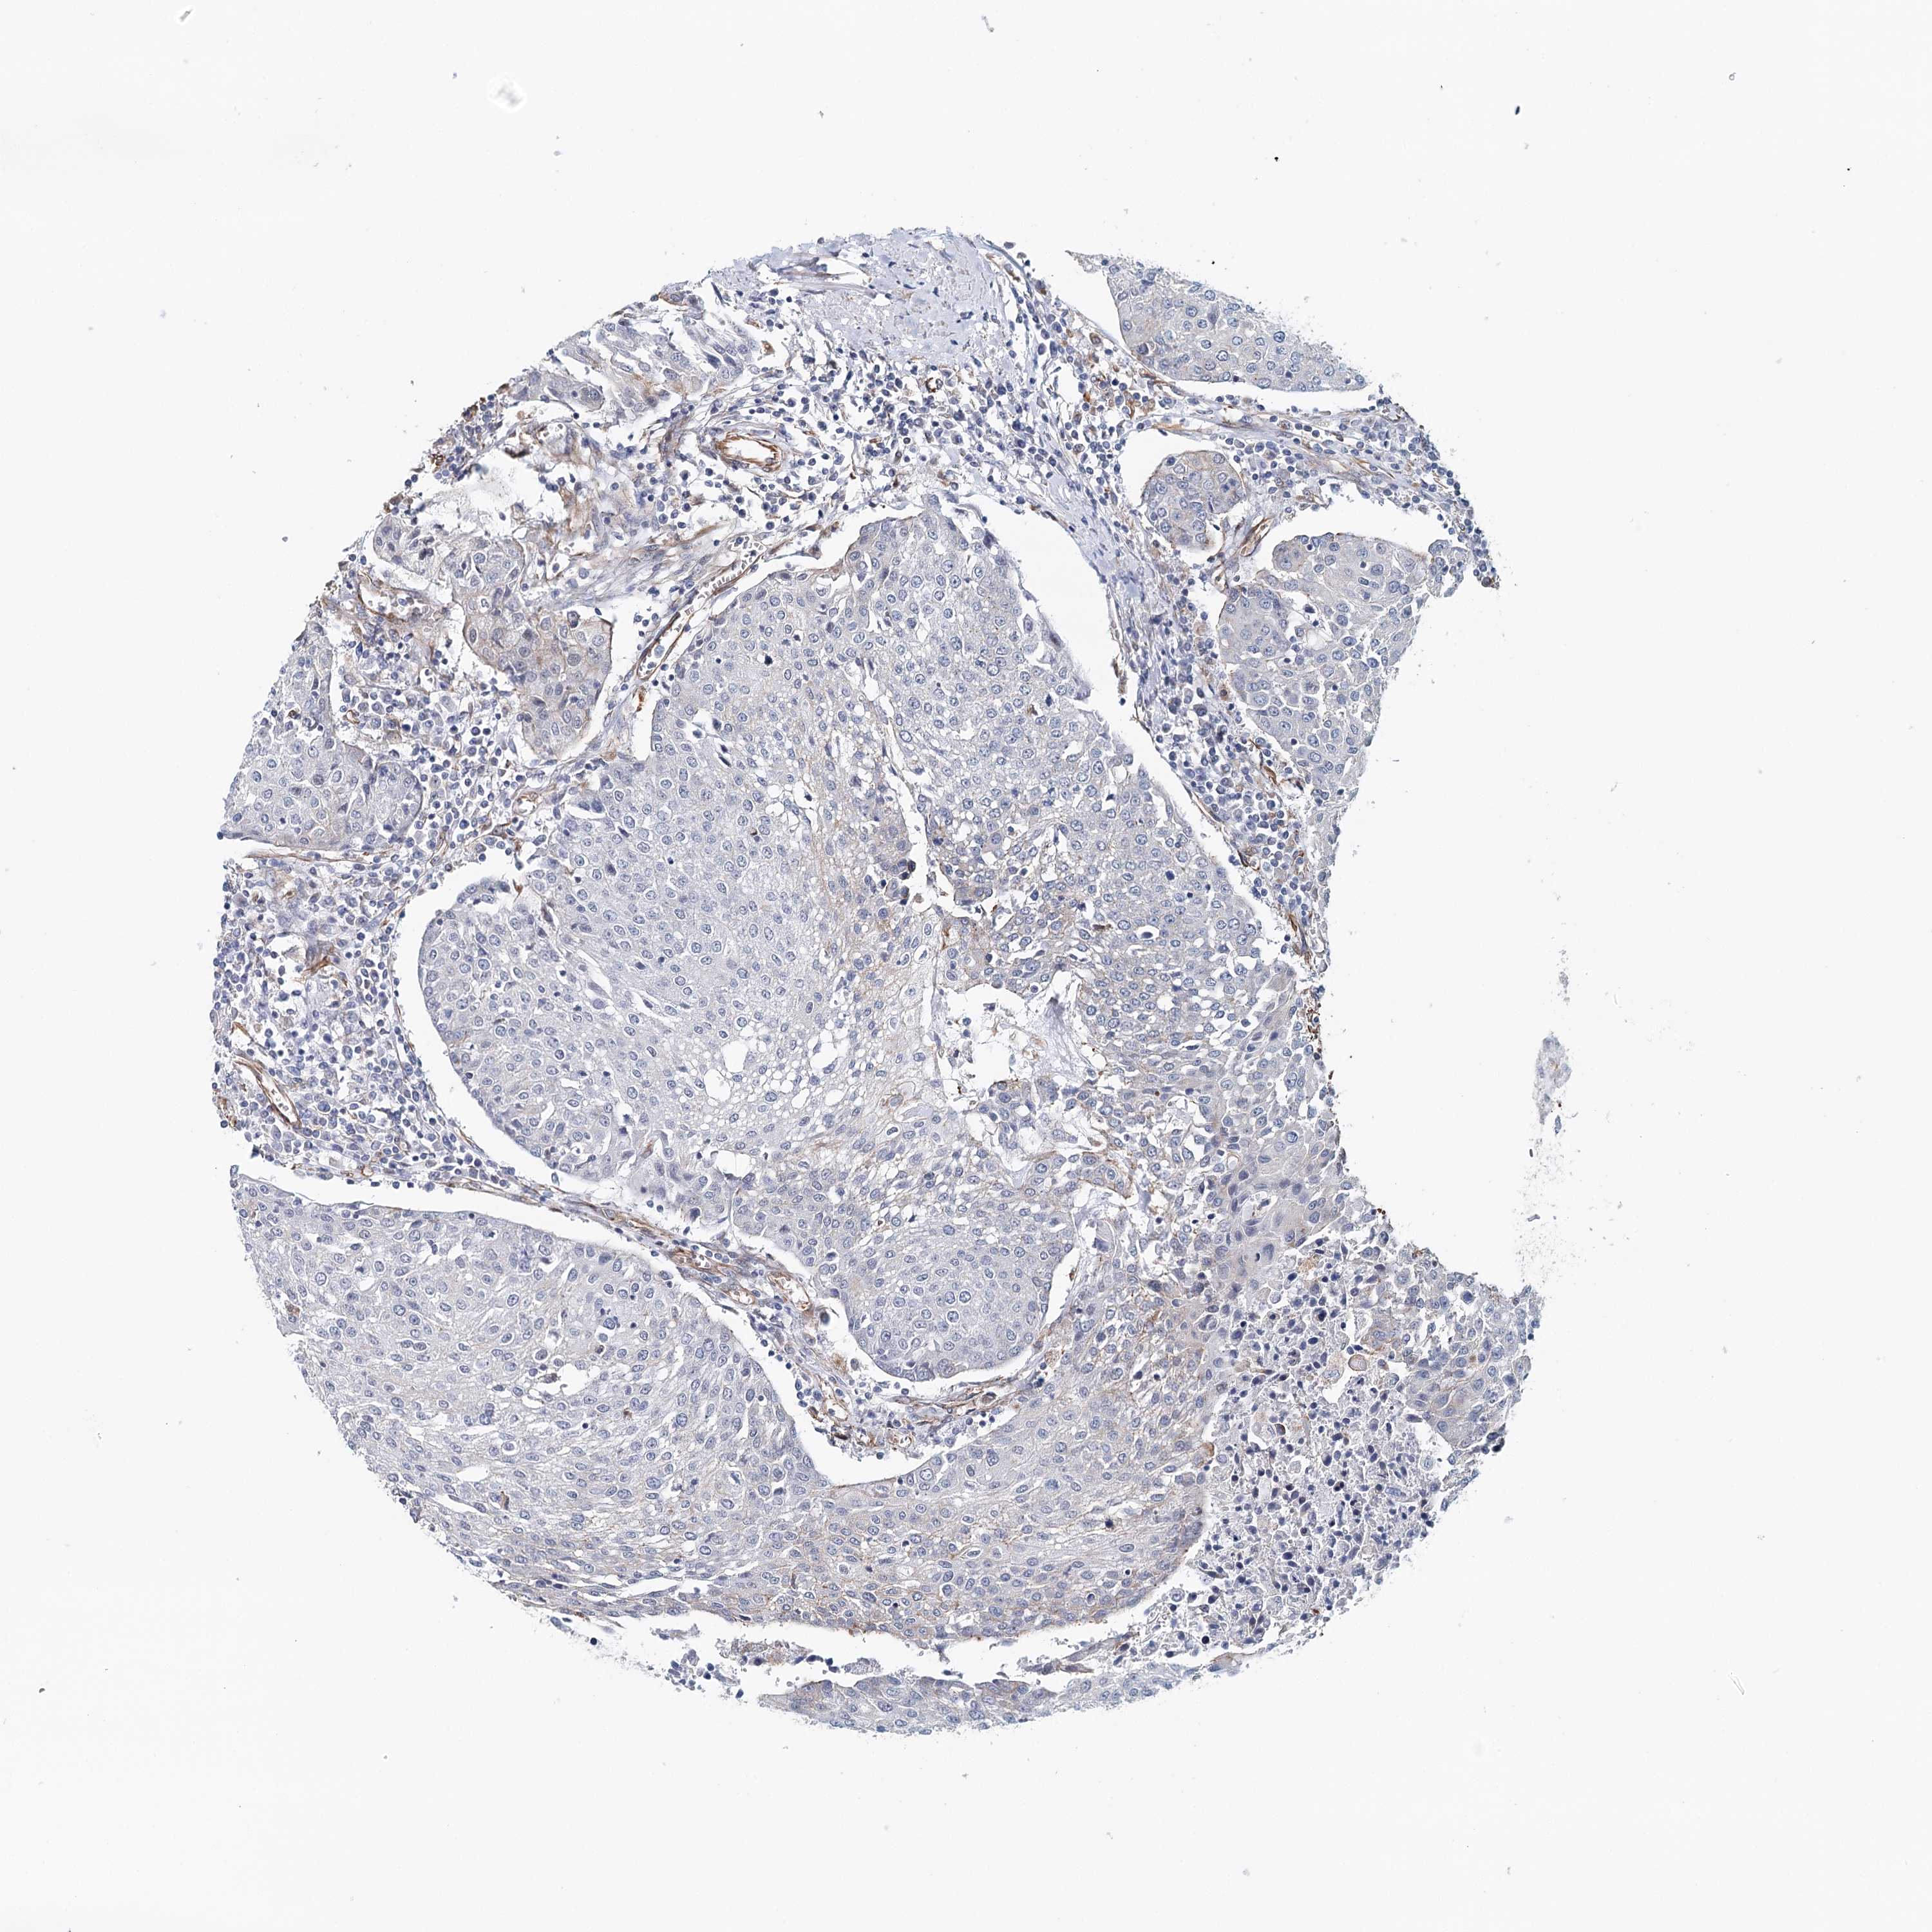

UROTHELIAL CANCER - Protein expressioni

A mouse-over function shows sample information and annotation data. Click on an image to view it in a full screen mode. Samples can be filtered based on level of antibody staining by selecting one or several of the following categories: high, medium, low and not detected. The assay and annotation is described here.

Note that samples used for immunohistochemistry by the Human Protein Atlas do not correspond to samples in the TCGA dataset.

Antibody stainingi

Antibody staining in the annotated cell types in the current human tissue is reported as not detected, low, medium, or high, based on conventional immunohistochemistry profiling in selected tissues. This score is based on the combination of the staining intensity and fraction of stained cells.

Each image is clickable and will lead to virtual microscopy that enables deeper exploration of all samples and also displays staining intensity scores, fraction scores and subcellular localization as well as patient and tissue information for each sample.

Antibody HPA071347

Urothelial carcinoma, High grade

Urothelial carcinoma, Low grade

Urothelial carcinoma, NOS